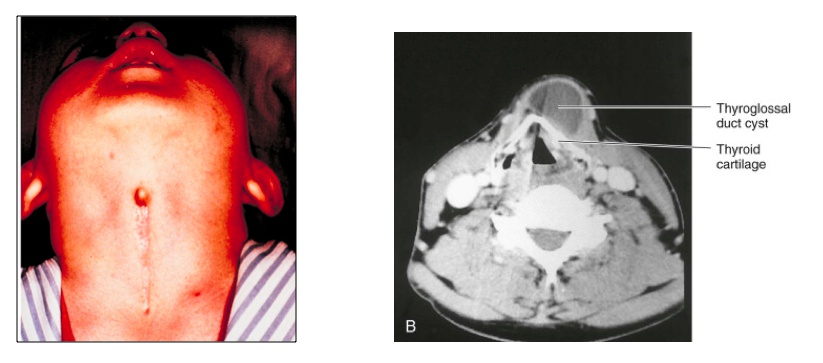

Thyroglossal duct

_The thyroid remains connected to the tongue via this duct during thyroid development and migration, which later obliterates.

Typically regresses, but may form the adult pyramidal lobe of the thyroid.

Foramen cecum indicates the former site of the duct.,

A thyroglossal duct cyst/sinus occurs when part of the thyroglossal duct fails to obliterate correctly, subsequently forming a cyst or sinus.

_Is commonly located ventral to the hyoid bone and laryngeal cartilage.,